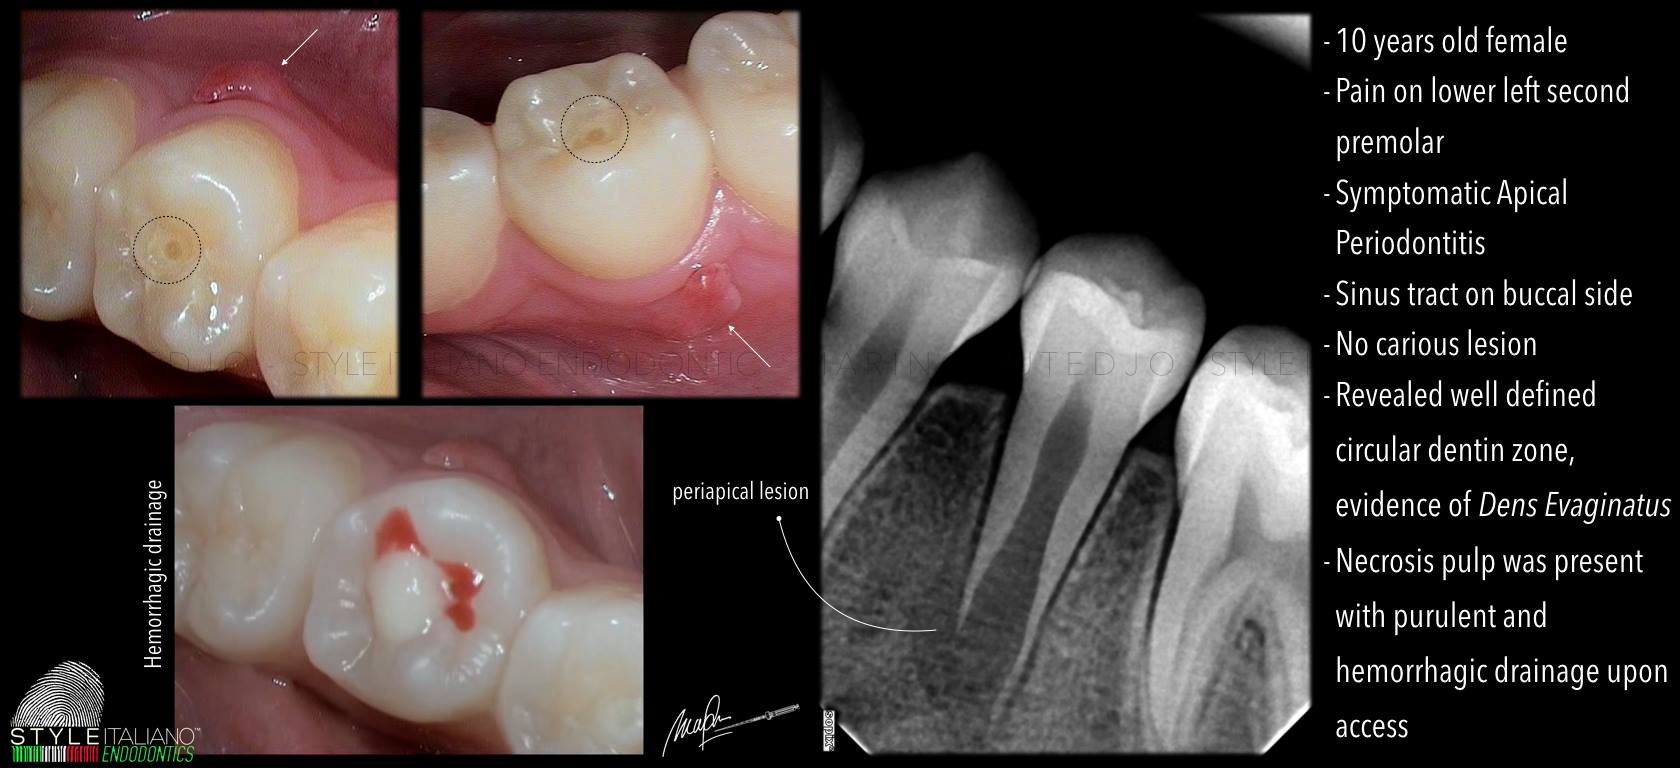

Núm phụ mặt nhai là một bất thường phát triển răng, thuộc nhóm Dens evaginatus, biểu hiện bằng một múi dư nhô lên ở mặt nhai, thường gặp nhất ở răng tiền cối hàm dưới (Leong’s premolar). Về mặt mô học, núm phụ này có thể chứa: Men, Ngà Và đặc biệt: một phần mô tủy kéo dài vào trong núm. Chính yếu tố này khiến núm phụ mặt nhai trở thành nguy cơ cao gây biến chứng nội nha, đặc biệt ở bệnh nhân trẻ.

Dễ gãy hoặc mòn núm phụ → lộ tủy

Gây viêm tủy sớm khi răng chưa đóng chóp

Có thể dẫn đến:

- Hoại tử tủy không triệu chứng

- Viêm quanh chóp mạn tính